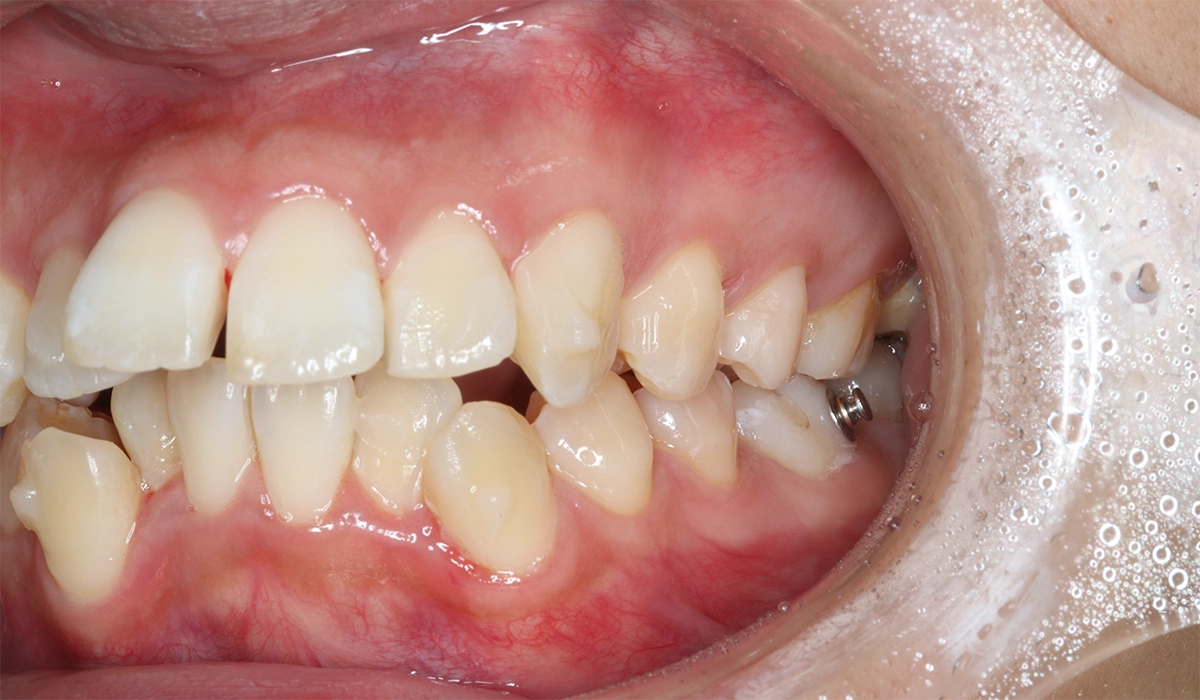

術前:右側

術前:左側